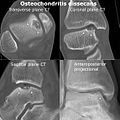

X-rays show lucency of the ossification front in juveniles. In older people, the lesion typically appears as an area of osteosclerotic bone with a radiolucent line between the osteochondral defect and the epiphysis. The visibility of the lesion depends on its location and on the amount of knee flexion used. Harding described the lateral X-ray as a method to identify the site of an OCD lesion.[36]

Magnetic resonance imaging (MRI) is useful for staging OCD lesions, evaluating the integrity of the joint surface, and distinguishing normal variants of bone formation from OCD by showing bone and cartilage edema in the area of the irregularity. MRI provides information regarding features of the articular cartilage and bone under the cartilage, including edema, fractures, fluid interfaces, articular surface integrity, and fragment displacement.[37][38] A low T1 and high T2 signal at the fragment interface is seen in active lesions. This indicates an unstable lesion or recent microfractures.[30] While MRI and arthroscopy have a close correlation, X-ray films tend to be less inductive of similar MRI results.[38]

Computed tomography (CT) scans and Technetium-99m bone scans are also sometimes used to monitor the progress of treatment. Unlike plain radiographs (X-rays), CT scans and MRI scans can show the exact location and extent of the lesion.[39] Technetium bone scans can detect regional blood flow and the amount of osseous uptake. Both of these seem to be closely correlated to the potential for healing in the fragment.[40][41]